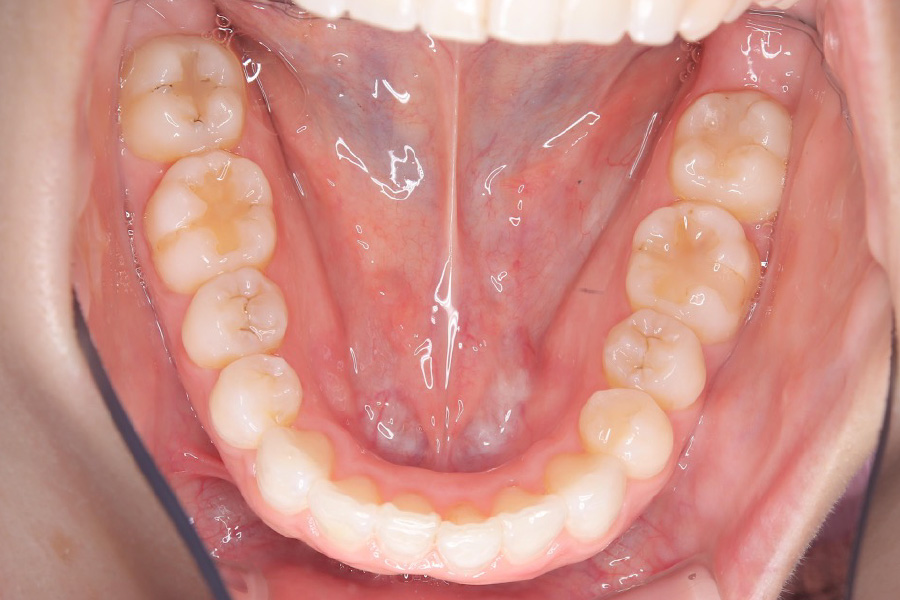

治療前

主訴 下の歯のガタつき、前歯の突出感が気になる

治療内容 インビザライン矯正

非抜歯